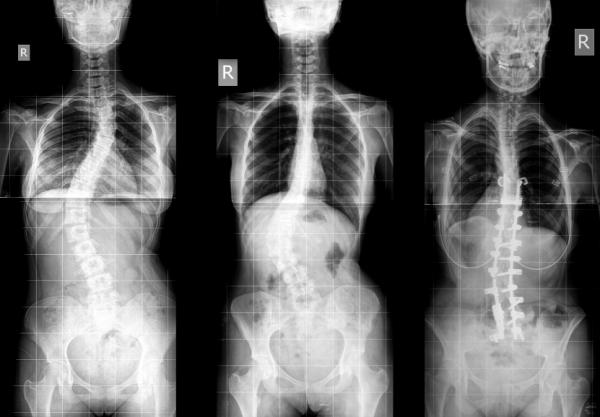

La escoliosis es una deformación en sentido lateral de la columna vertebral y se presenta en los niñ@s durante la etapa de crecimiento, siendo este el principal factor de evolución de las deformidades.

En la edad adulta pueden presentarse deformidades, dolores y alteraciones posturales compensatorias.

Las consecuencias de la escoliosis son principalmente un aspecto físico indeseado (gibosidades costales, xifosis), alteraciones posturales compensatorias dolores, complicaciones cardiopulmonares .